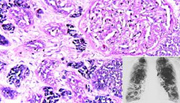

Страшный вирус назвали по имени

Гонконгские ученые сделали крупный прорыв в раскрытии тайны дыхательной болезни, которая стала причиной гибели уже, по меньшей мере, девяти человек и вызвала панику в медицинских и околомедицинских кругах всего мира.

Болезнь известная как "Серьезный Острый Дыхательный Синдром" (СОДС) была идентифицирована. Ее вызывает вирус из семейства Paramyxoviridae (парамиксовирусов). Это установили исследователи из гонконгской больницы принца Уэльского и Китайского университета.

"Важнейший вывод медиков заключается в том, что тактика антивирусного лечения была выбрана правильно", - заявил Сидни Чун Шеун-чи, декан медицинского факультета Китайского университета в интервью газете South China Morning Post.

Однако врачи подчеркивают, что в семейство парамиксовирусов входят различные возбудители болезней, которые могут в той или иной мере затрагивать людей. В частности, к этому семейству вирусов относятся возбудители кори, свинки и собачья чумка.

Для того, чтобы точно определить является ли СОДС новым вирусом и излечим ли он, потребуются дополнительные исследования. Пока же эту болезнь продолжают именовать как атипичная пневмония или гриппоподобное вирусное заболевание.